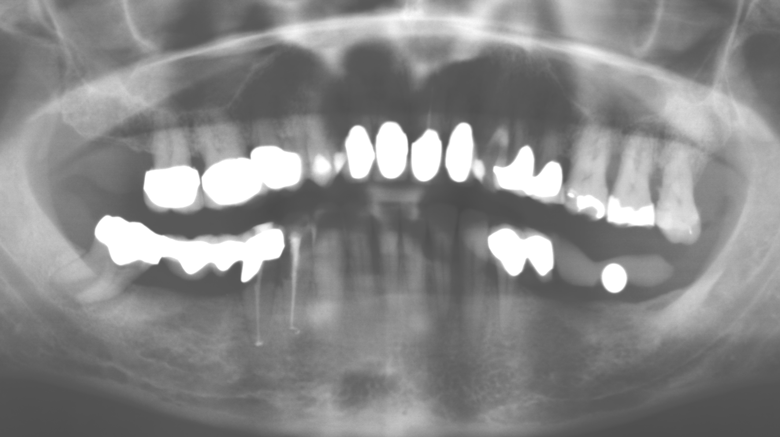

A 52-year-old patient presented in our clinic for the first time in 2004 following tooth loss in the third quadrant, expressing a desire for a new prosthetic restoration. Periodontal and radiological diagnostics revealed the need for extensive periodontological treatment. In addition, teeth 48, 28 and 27 were attributed a very poor prognosis and were subsequently extracted (Fig. 1). Following the successfully completed, systematic periodontological treatment, a fixed dental implant was inserted with the introduction of five implants in tooth regions 35, 36, 37, 46 and 47. Prosthetic treatment of the natural teeth was effected with veneered zirconium dioxide ceramic crowns; the implants were composed of two-piece, individual zirconium dioxide abutments and similarly veneered crowns made of a zirconium dioxide ceramic (Cercon base colored, Dentsply Sirona Lab). Definitive insertion of the prosthetic restoration occurred in 2005.